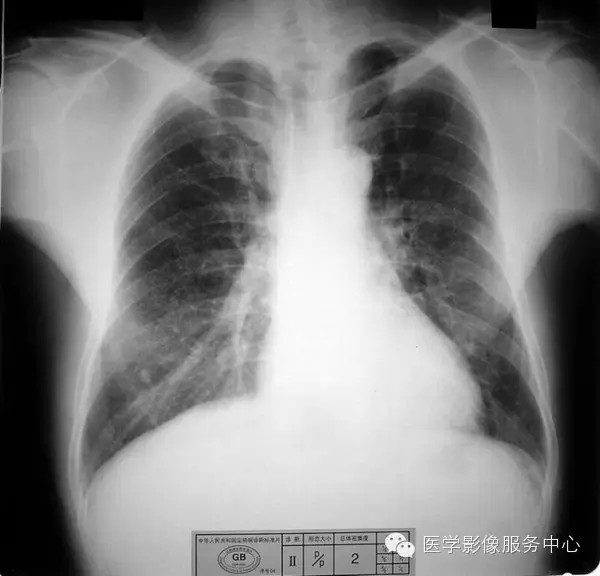

4.3 二期尘肺(Ⅱ)

a)Ⅱ:有总体密集度2级的小阴影,分布范围超过4个肺区;或有总体密集度3级的小阴影,分布范围达到四个肺区。

b)Ⅱ :有总体密集度3级的小阴影,分布范围超过4个肺区;或有小阴影聚集;或有大阴影,但尚不够诊断为Ⅲ者。